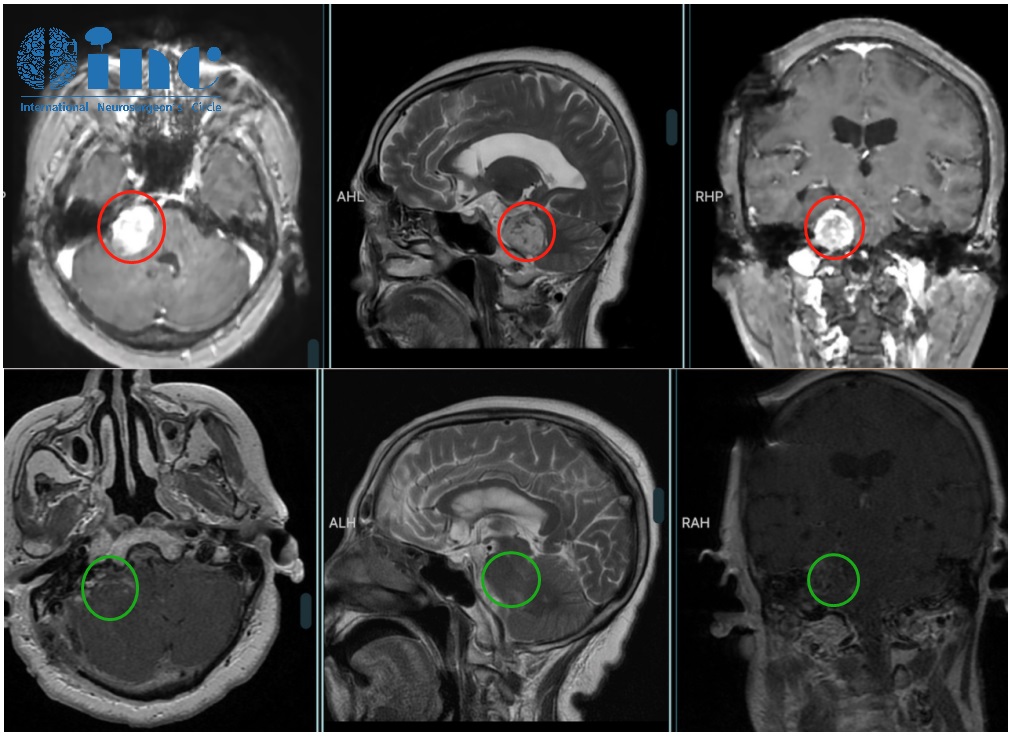

聽神經(jīng)瘤案例——術(shù)前術(shù)后影像

術(shù)前術(shù)后影像對比,齊奶奶聽瘤得到全切

手術(shù)在神經(jīng)電生理監(jiān)測下順利進(jìn)行,巴教授順利為齊奶奶全切了腫瘤。